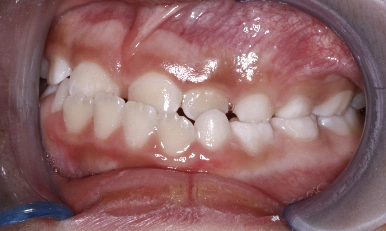

Patient Results